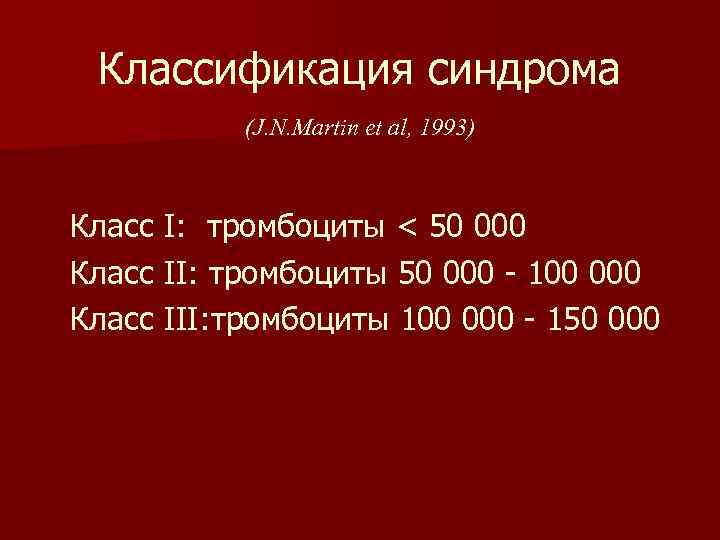

Классификация синдрома (J. N. Martin et al, 1993) Класс I: тромбоциты < 50 000 Класс II: тромбоциты 50 000 - 100 000 Класс III: тромбоциты 100 000 - 150 000

Классификация синдрома (J. N. Martin et al, 1993) Класс I: тромбоциты < 50 000 Класс II: тромбоциты 50 000 - 100 000 Класс III: тромбоциты 100 000 - 150 000